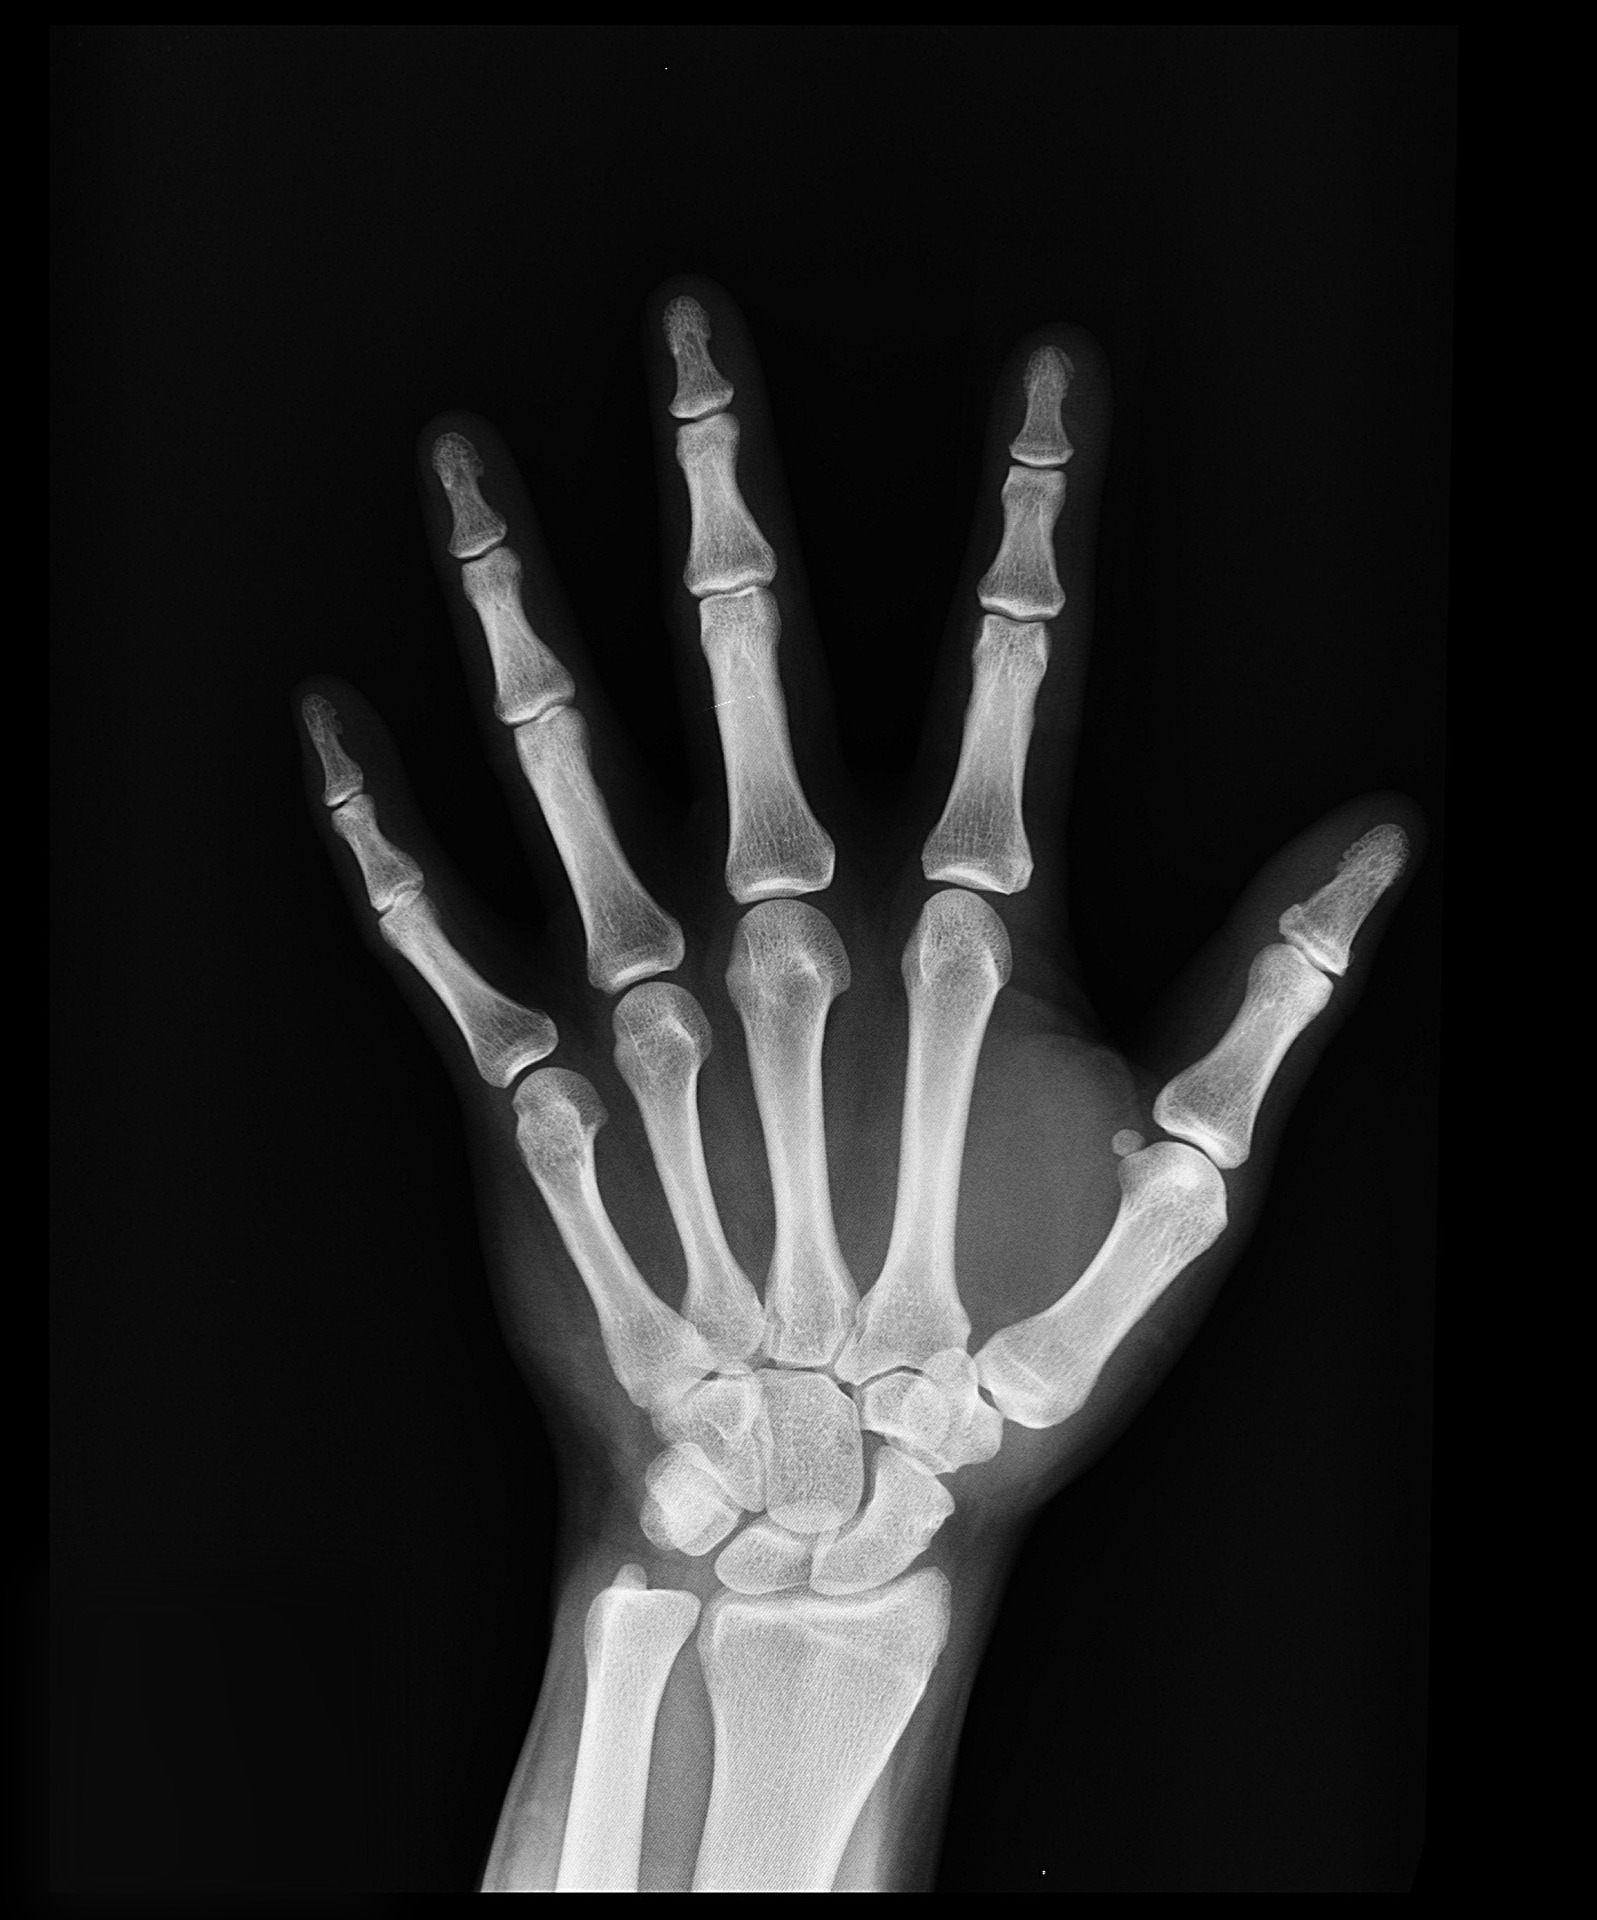

뼈에 구멍이 많이 생긴다고 해서 골다공증이라고 합니다. 골다공증은 뼈가 약해지고 얇아져서 잘 부러지는 질환을 의미합니다. 35세부터 골량이 줄어들어 폐경 전후로 급격히 골량이 줄어듭니다. 폐경 후 2-3년이 뼈의 소실이 가장 많이 일어납니다. 골다공증은 뼈가 부러질 때까지 아무런 변화를 느끼지 못합니다. 그래서 폐경기가 되면 뼈의 건강을 확인해야 할 것입니다.심할경우 허리를 구부리거나 기침을 하는 등 일상생활에서 뼈가 쉽게 부러질 수 있습니다.

뼈가 부러지거나 골다공증의 가족력, 폐경, 비타민D 결핍, 신체적으로 비활동적인 사람, 과도한 음주를 하시는 사람, 특정한 약물을 복용하시는 사람, 칼슘의 흡수장애가 있는 사람 등이 골다공증에 걸릴 수 있습니다. 뼈 하나가 부러지면 더 많은 뼈가 부러져 장기적인 장애과 독립성을 잃을 위험이 높아지기 때문에 조기 진단이 필요합니다.

골다공증이 있는 경우 윗몸일으키기 또는 골프 스윙과 척추를 비틀 거아 허리를 숙이는 운동 피하는 게 좋습니다. 골절은 골다공증의 심각한 합병증입니다. 주로 척추와 고관절이 잘 골절됩니다. 뼈가 약해지면 적절한 운동과 약물치료로 골형성을 유지해야 할 것입니다.